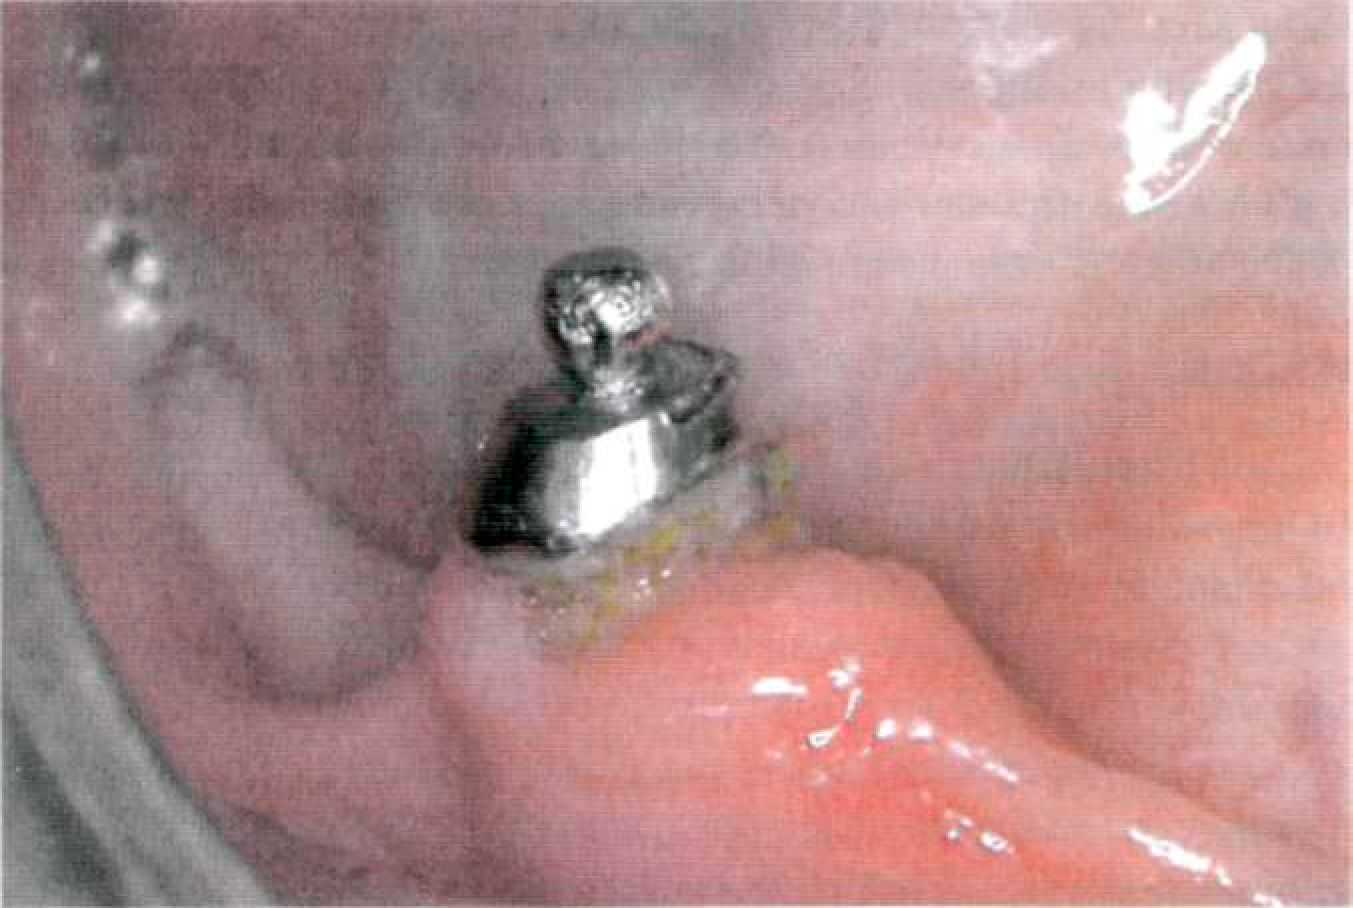

Этап 11. Фиксация культевой вкладки с супрарадикулярным аттачменом на цемент проводится под контролем съемной части (рис. 147). Наложение протеза сопровождается рекомендациями о пользовании протезом, правилах гигиены и сроках контрольных осмотров. Одним из осложнений при применении покрывных протезов с супрарадикулярными аттачменами является развитие кариеса корня (рис. 148). В первую очередь, это происходит из-за неудовлетворительной гигиены полости рта, так как пациенты этой группы — чаще всего достаточно пожилые люди.